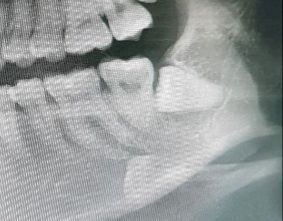

※처음 사랑니 진단받을때 찍었던거라 대충 3년전쯤 사진입니다

대학병원 가서 빼려고 했는데, 교수님이 신경이랑 매우 가까운 위치라서 입술 감각이 평생 이상해질수 있다고 꼭 뺄거냐고 하시길래 무서워서 안빼고 집에 왔습니다

그 전에 같은병원에서 다른쪽 사랑니 뺐을땐(제눈에는 그 사랑니도 거의 비슷하게 신경 바로 옆으로 보였는데 3d로는 달랐을지도 모르겠어요) 교수님이 딱히 별말 안하시고 바로 마취하고 뽑아주셨었는데 이번엔 경고를 해주시니 신경이랑 더 가깝나 싶어서 무섭구요